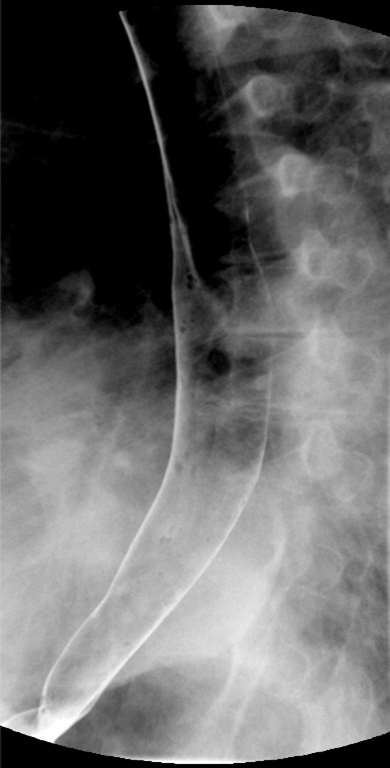

- Method—Thoracic:

- With the patient standing upright, have them turn into a left posterior oblique position.

- Instruct the patient that you will be handing them a cup containing a small amount of water and effevescent crystals and that they should drink it as quickly ask possible.

- As soon as the patietn has finished the water, exchange the empty cup for a cup of thick barium.

- Ask the patient to drink two (2) sips of thick barium. The patient does not need to drink this quickly.

- After the patient has begun drinking, take images of the upper and lower esophagus distended and coated with barium

(key image 5)

(key image 6)

(key image 7).

- Have the patient turn into the right posterior oblique position.

- Repeat steps 3 and 4, only this time the patient will take the barium in their right hand

(key image 8)

(key image 9)

(key image 10).